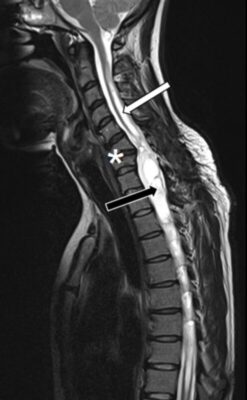

- Dị tật Chiari type I: Đây là nguyên nhân phổ biến nhất ở người lớn. Sự sa xuống của hạnh nhân tiểu não qua lỗ chẩm gây cản trở dòng chảy CSF ở ngã ba sọ-cổ, dẫn đến thay đổi áp lực và tạo syrinx, thường ở tủy cổ.

(Ghi chú: Dị tật Chiari là tình trạng một phần của não sau, chủ yếu là hạnh nhân tiểu não, bị lệch chỗ xuống dưới lỗ chẩm. Có nhiều type khác nhau, được phân loại dựa trên mức độ sa lệch và các cấu trúc não bị ảnh hưởng. Chiari Type I là type phổ biến nhất, thường được chẩn đoán ở thanh thiếu niên hoặc người trưởng thành. Đặc trưng bởi sự sa xuống của hạnh nhân tiểu não ít nhất 5mm dưới mặt phẳng của lỗ chẩm. Thân não và não thất tư thường ở vị trí bình thường.) - Sau chấn thương tủy sống: Syringomyelia có thể phát triển muộn (vài tháng đến nhiều năm) sau chấn thương tủy sống, do viêm dính màng nhện, xơ hóa, hoặc rối loạn vi tuần hoàn và dòng chảy dịch não tuỷ.

- Chụp cộng hưởng từ (MRI): Là tiêu chuẩn vàng để chẩn đoán.

- Chuỗi xung T1-weighted: Syrinx thường giảm tín hiệu.

- Chuỗi xung T2-weighted: Syrinx tăng tín hiệu rõ rệt, cho thấy hình ảnh khoang chứa dịch.

- Tiêm thuốc đối quang từ (Gadolinium): Giúp xác định các nguyên nhân kèm theo như khối u, viêm nhiễm.

- MRI Cine flow: Có thể đánh giá động lực học dòng chảy CSF ở ngã ba sọ-cổ, đặc biệt hữu ích trong trường hợp nghi ngờ dị tật Chiari.

- Giải ép hố sau (Posterior fossa decompression): Cho các trường hợp liên quan đến dị tật Chiari type I. Mục tiêu là tái lập dòng chảy CSF bình thường ở ngã ba sọ-cổ. Tỷ lệ ổn định bệnh có thể đạt 70-80% hoặc cao hơn trong nhiều nghiên cứu.